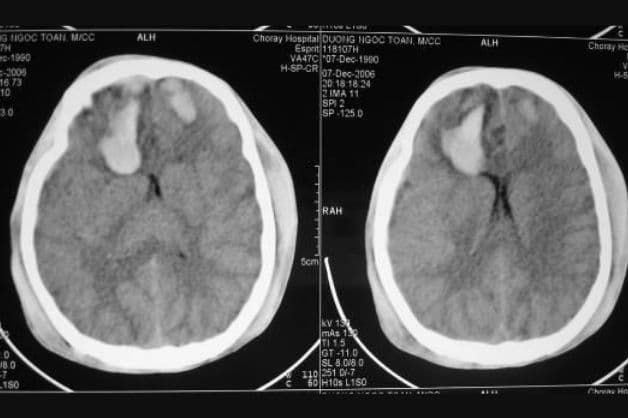

Hình ảnh tổn thương não ở bệnh nhân sau khi thực hiện chụp cắt lớp vi tính sọ não

– Khối choán chỗ trong sọ não: Khối choán chỗ có thể xuất hiện bằng cách thay đổi tỷ trọng hoặc tạo thành các hiệu ứng bên trong sọ não. Khi có các dấu hiệu này, người bệnh có thể gặp các vấn đề về u não, ổ xuất huyết não, phù não, ổ áp xe hoặc khối máu tụ nội sọ.

– Thay đổi tỷ trọng mô não: vùng tăng tỷ trọng (đám xuất huyết, ổ máu tụ hoặc dạng u não), vùng giảm tỷ trọng (áp xe não, nhồi máu não hoặc di căn ung thư), nốt vôi hóa (u não, u thần kinh đệm hoặc sán não), đồng tỷ trọng.